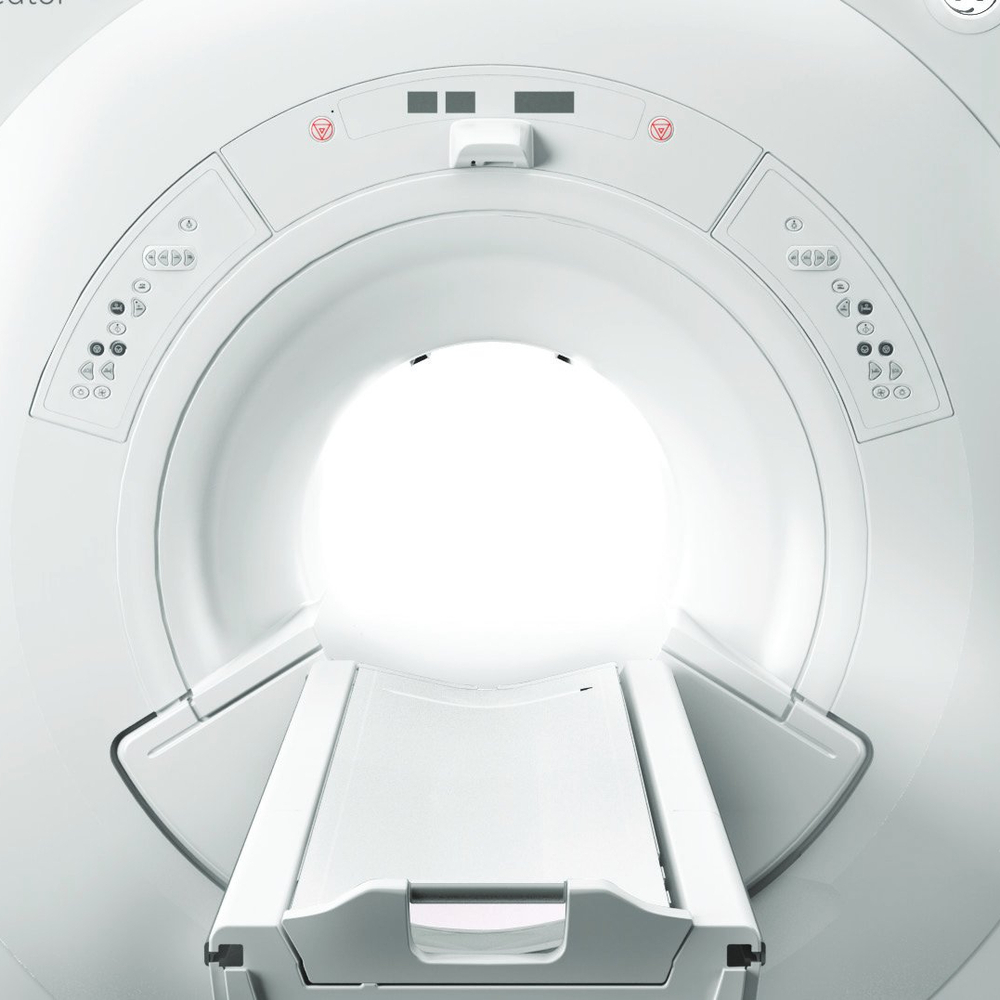

| Тип магнита | Сверхпроводящий магнит с широким тоннелем |

| Диаметр тоннеля для пациента | 70 см |